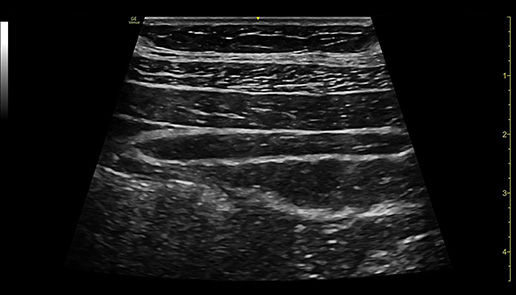

Automatically recall parameter settings with Follow Up

Delivering consistent and clear conclusions for repeated exams on the same patient, Follow Up automatically recalls parameter settings from a previous exam including comments and body patterns. It also supports monitoring of patient response to treatment over time, allowing a side-by-side view of historical and new images.